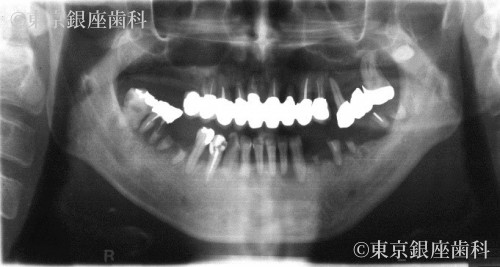

5年後に来院した際には、歯周病が悪化し著しい歯の揺れ、歯の破折、骨の吸収が見られた。

歯周病の進行により歯に動揺があり長期の保存が難しくこのままでは予後が不安であった為全顎的な治療が必要と判断。

上下全ての歯を抜歯。

重度の歯周病により骨が吸収されているため、上顎骨が薄く右側は上顎洞に骨を足す治療(サイナスリフト)を行い上顎に5本、下顎に4本のインプラントを埋入しワンデイインプラントを行った。